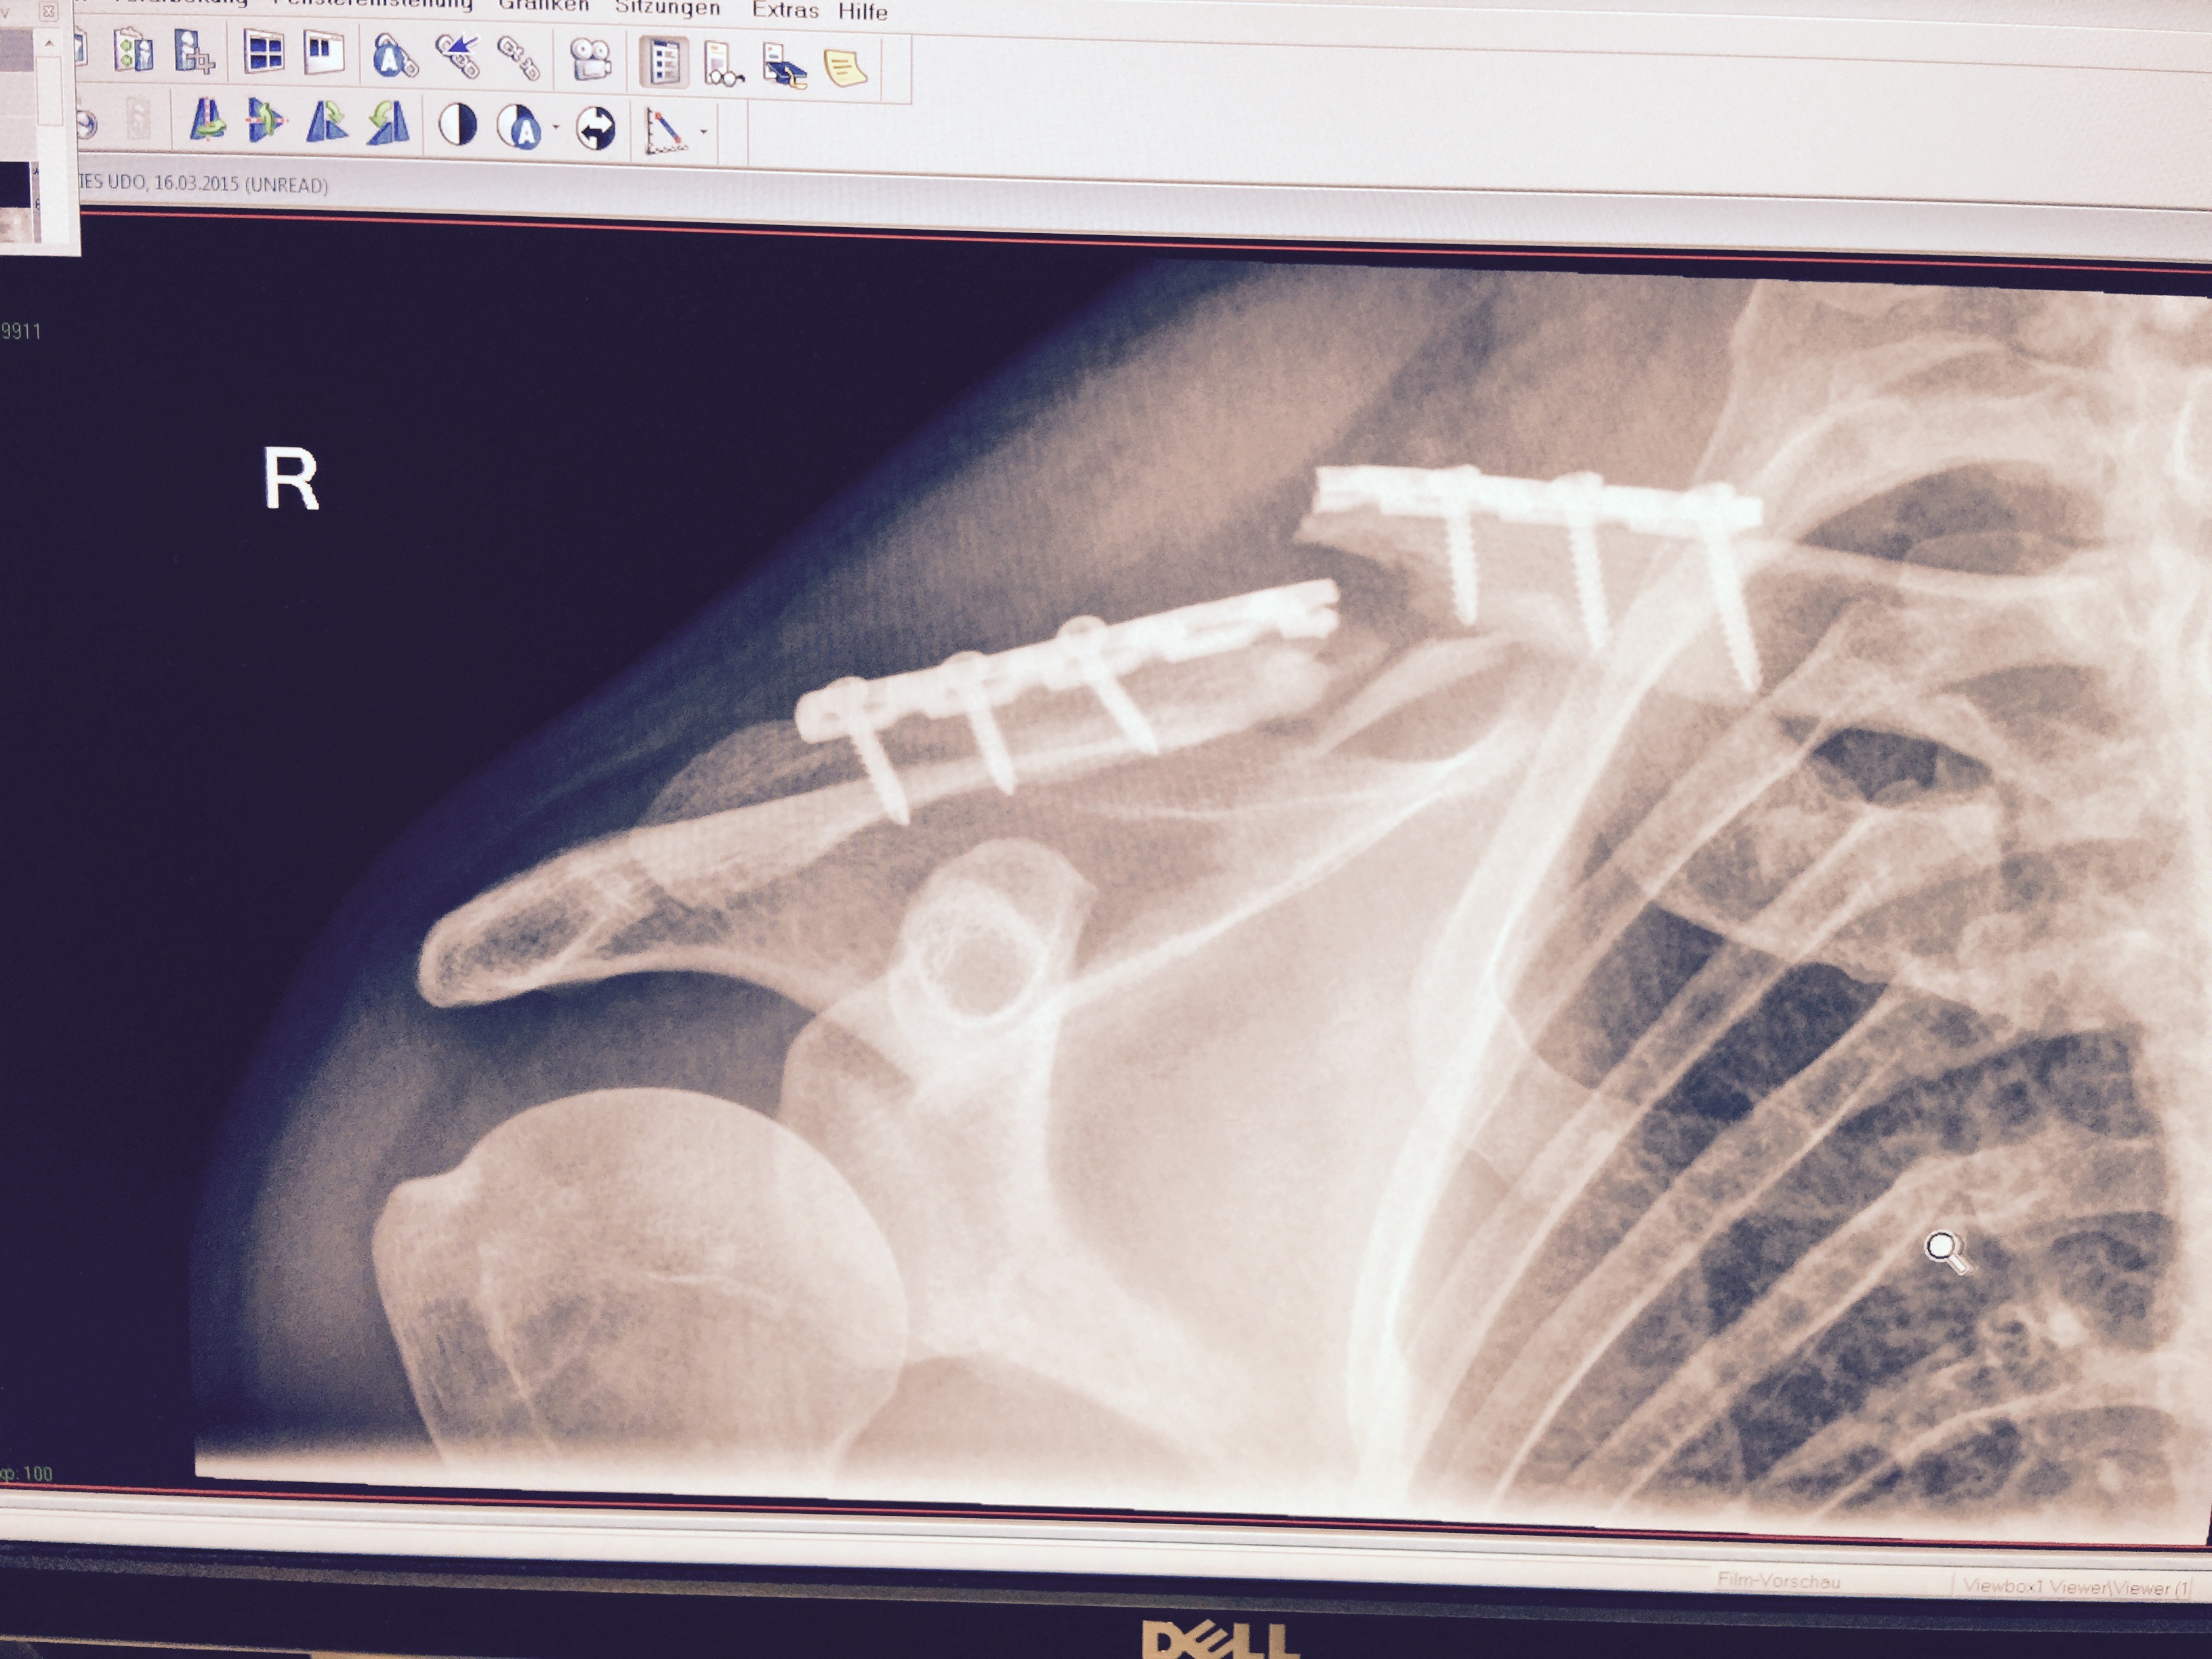

Udo-MH hat geschrieben:Also ich kann ja mal meine 2 cent beisteuern. Auch wenn es nicht das gleiche ist. Ich hatte einen Clavicula RE Trümmerbruch. Die Erste OP war gelaufen und mir wurde eine viel zu dünne Titanplatte eingeschraubt. Die Trümmer von der Assiärztin mit Nähfaden umwickelt. Wenn gewünscht hau ich auch Röntgenfotos rein, was aber für mich zweitrangig ist.

Ok. Erste Platte nach 3 Montaen und der Entfernung des Gilchristverbandes gebrochen. 2. OP. Dickere Platte und Knochenchips aus dem Beckenkamm zu einen Ei geformt um den Bruch. Weil der erste Versuch gescheitert war wurde "nachgefragt". Ich nehme alle 2-3 Tage Diclofenac wegen meines Bandscheibenvorfalls. Das hätte ich lt. Chefarzt NICHT nehmen dürfen. Es verhindert Callusbildung (Knochenverheilung). Dieser Heilprozess ist einer Entzündung gleichzusetzen. Da ich nun Entzündungshemmer nahm war das Ergebnis gleich null.

Die Platte ist nun schon seit ca. 2,5 Jahren drin und ich werde sie wohl auch nicht entfernen lassen. Da in 80% der OP´s das Schlüsselbein wieder bricht.